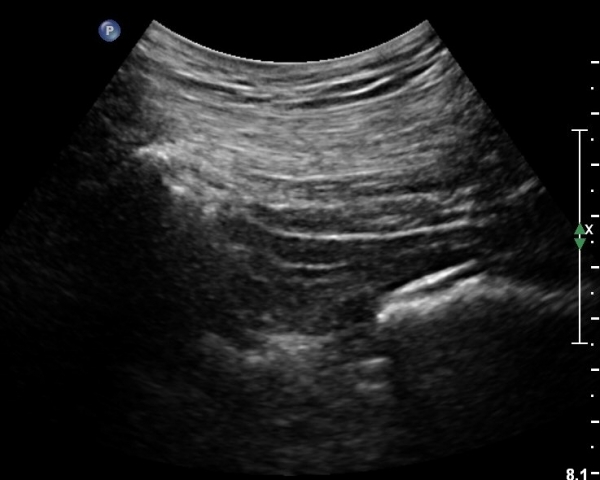

ŽÃÍÀÚ¸¦ ´Ù¸®ÂÊÀ¸·Î ¼öÆò À̵¿ÇÏ¸é ½ÉÃþ¿¡¼­ Àå°ñÀÌ »ç¶óÁö°í »õ·Î¿î ±ÙÀ°ÃþÀÌ º¸À̴µ¥ À̰ÍÀÌ ÀÌ»ó±ÙÀ̰í ÀÌ»ç±Ù ½ÉÃþ¿¡¼­ Á°ñ½Å°æ¸£ °üÂûÇÒ ¼ö ÀÖ´Ù(»çÁø 2, 3).